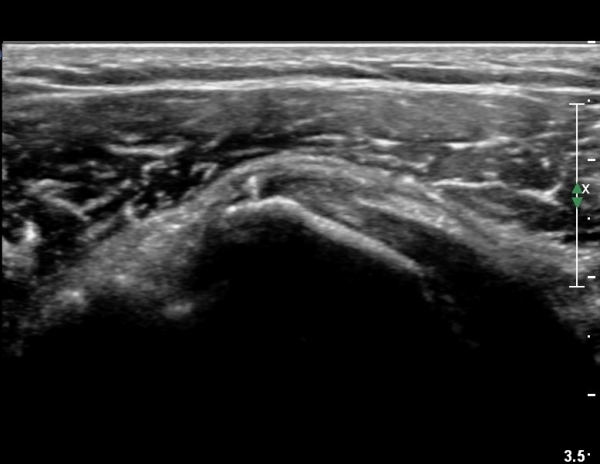

ÀÌµÎ¹Ú±Ù°Ç Á¾´Ü¸é°Ë»ç¿¡¼­ °üÀý³» ¼ö¾×Àú·ù°¡  °üÂûµÈ´Ù(»çÁø 3).